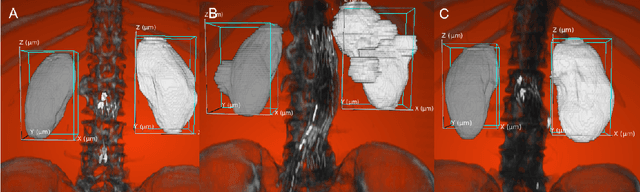

Abstract:Organ localization can be challenging considering the heterogeneity of medical images and the biological diversity from one individual to another. The contribution of this paper is to overview the performance of the object detection model, YOLOv3, on kidney localization in 2D and in 3D from CT scans. The model obtained a 0.851 Dice score in 2D and 0.742 in 3D. The SSD, a similar state-of-the-art object detection model, showed similar scores on the test set. YOLOv3 and SSD demonstrated the ability to detect kidneys on a wide variety of CT scans including patients suffering from different renal conditions.